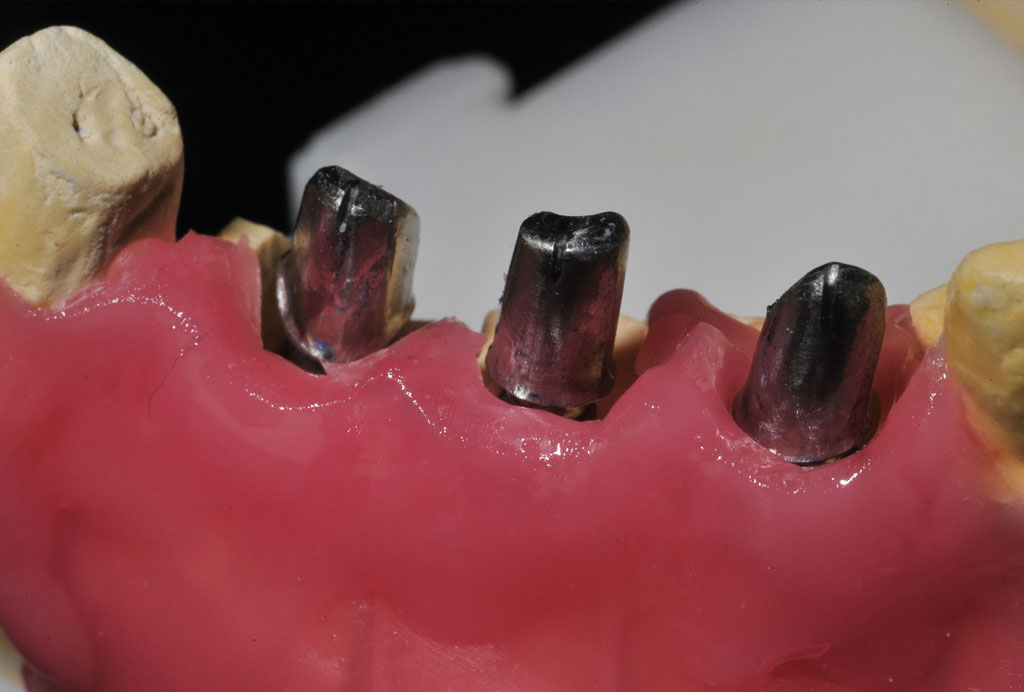

Fehlen in der Front oder im Seitenzahnbereich mehrere Zähne, ist eine Brücke oder Prothese vollkommen unnötig. Die fehlenden Zähne können entweder einzeln durch eine entsprechende Anzahl von Implantaten oder durch implantatgetragene festsitzende Brücken ersetzt werden. Das Bild der Kronen zeigt die drei Verschraubungen deutlich, im Mund liegen diese verdeckt am Gaumen oder im Bereich der Zunge.